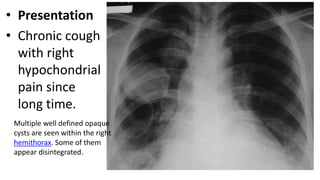

• Presentation

• Chronic cough

with right

hypochondrial

pain since

long time.

Multiple well defined opaque

cysts are seen within the right

hemithorax. Some of them

appear disintegrated.